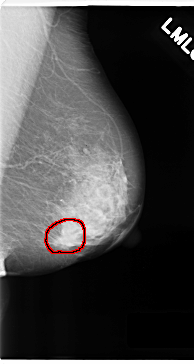

C_0180_1.RIGHT_MLO

LEFT_MLO LINES 4720 PIXELS_PER_LINE 2512 BITS_PER_PIXEL 12 RESOLUTION 50 OVERLAY

FILE: C_0180_1.LEFT_MLO.OVERLAY

TOTAL_ABNORMALITIES 1

ABNORMALITY 1

LESION_TYPE MASS SHAPE LOBULATED MARGINS SPICULATED

ASSESSMENT 5

SUBTLETY 5

PATHOLOGY MALIGNANT

TOTAL_OUTLINES 1

BOUNDARY